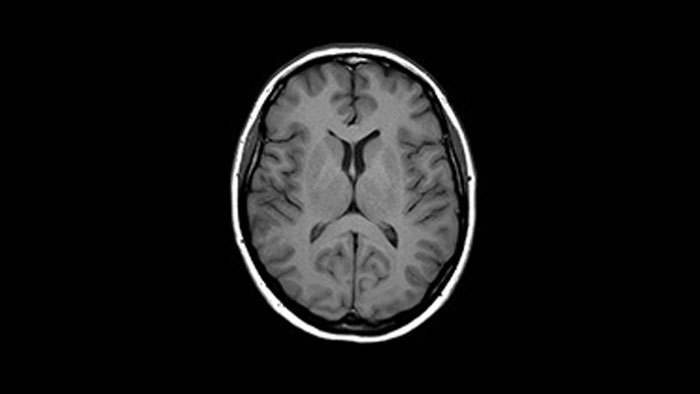

Brain with glioblastoma